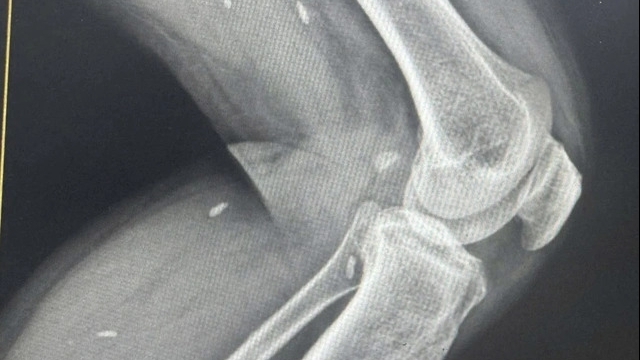

Theo bác sĩ Phạm Duy Linh, Khoa Phẫu thuật tạo hình Thẩm mỹ, Bệnh viện đa khoa Đức Giang (Hà Nội), khi tiếp nhận bệnh nhân, bác sĩ nhận thấy mép khâu không chuẩn, kỹ thuật khâu không tốt nên gây xô lệch trên da; Chẩn đoán bệnh nhân nhiễm trùng, hoại tử da ở vùng ngực, vết mổ chậm lành, chảy dịch. Nếu không được điều trị kịp thời, vết thương bị nhiễm trùng lâu dài sẽ tạo thành sẹo xấu.

| Bệnh nhân được xử trí kịp thời tại Bệnh viện đa khoa Đức Giang |

Bệnh nhân được điều trị kháng sinh, cải thiện tình trạng nhiễm trùng. Khi vết mổ không còn chảy dịch, người bệnh sẽ được phẫu thuật sửa sẹo, nắn lại các vùng khâu bị xô lệch.